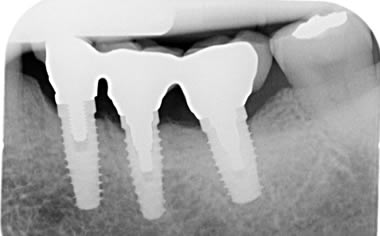

Case Two (5 images)

Six missing lower back teeth replaced by dental implants